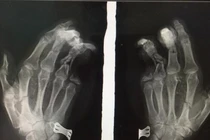

BS. Nguyễn Hoàng Quân - Khoa Phẫu thuật Chi trên và Y học thể thao, Bệnh viện Hữu nghị Việt Đức - cho hay: Ngay sau khi tiếp nhận bệnh nhi, các bác sĩ đã nhanh chóng thăm khám xác định bé bị tổn thương phức tạp dập nát bàn tay trái, cụt chấn thương ngón II, III, đứt gân gấp sâu ngón IV, trật hở khớp bàn ngón III. Các bác sĩ đã tiến hành cắt lọc, găm kim, nối gân, sửa mỏm cụt cho bệnh nhi.

| Bác sĩ kiểm tra phim chụp Xquang của bệnh nhi (Ảnh - BVCC) |

Sau 4 ngày phẫu thuật, vết thương của bé đã khô, ngón tay 3,4 hồng hào. Bé đang tiếp tục được theo dõi và điều trị tại Khoa Phẫu thuật Chi trên và Y học thể thao, Bệnh viện Hữu nghị Việt Đức.